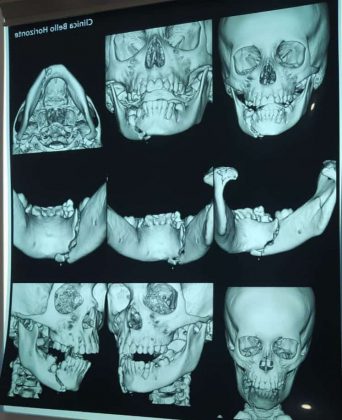

Un padre pide ayuda luego de que su menor hijo se cayera de un árbol cuando jugaba con sus hermanos. Según comenta la familia, la rama del árbol donde estaba el menor se ha quebrado, el menor ha caído sobre una piedra y se ha quebrado la mandíbula.

El hecho ocurrió el viernes 26 de mayo, pero recién ayer han podido sacar las placas que solicitaba el personal médico, esto por falta de dinero. El médico que atendió al niño mencionó que necesita ser operado de emergencia.